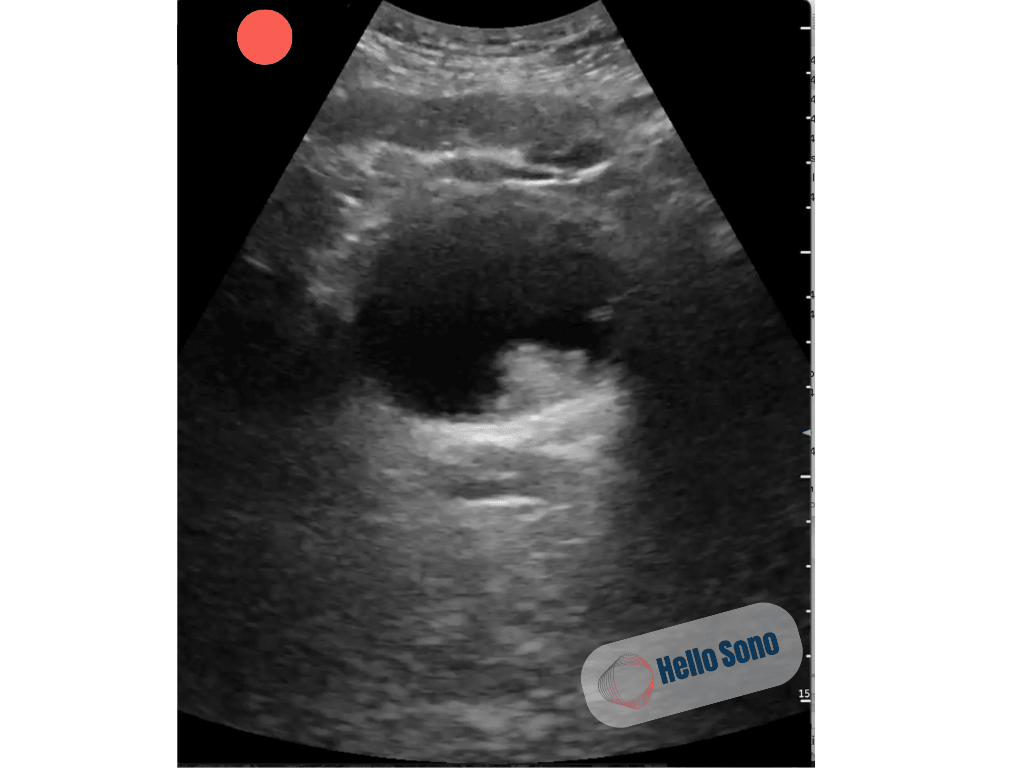

On exam, he was afebrile and well appearing, with mild right lower quadrant and flank tenderness. No palpable masses or scrotal abnormalities were appreciated. His prostate exam was normal. Given his urinary complaints, the provider performed a point-of-care ultrasound (POCUS) of the bladder and kidneys to evaluate for urinary retention and renal colic. A transverse view of the bladder is shown below.

Figure 1. This ultrasound image shows a transverse view of the bladder. Instead of an anechoic (black), smooth-walled bladder, an irregular hyperechoic mass can be seen protruding into the bladder lumen near the left ureterovesical junction.

The ultrasound clip reveals a hyperechoic, irregular intravesical mass, suspicious for a bladder malignancy.

In a healthy individual, bladder POCUS shows a symmetric, anechoic lumen with thin, smooth walls and no intraluminal masses.